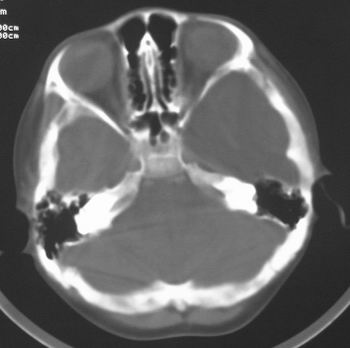

患儿,男,8岁,外伤2小时,无恶心、呕吐,四肢活动正常。既往无任何不适,智力发育正常。

典型的左中颅窝蛛网膜囊肿。

典型的左中颅窝蛛网膜囊肿。最常见的发病部位,张力比较高,相应颅板受压变薄。赶紧治疗,脑组织的功能可能部分恢复。